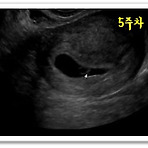

출산후 첫 출산을 하고난후 한달이라는 시간이 흘렀다. 이제부터가 전쟁인가라고 생각했는데 전쟁이라고 할수도 없었다.먼저 출산을 했던 언니들이나 주변 사람들의 말을 들어보면 아이낳을때부터 지옥시작이라고 하는데 사실 그부분을 느낄수가 없었기 때문이다. 친정이 집에서 가깝기도 했고 아이낳고 계속 친정에서 있었기 때문에 사실 많은부분 아이를 키우는데 처음에는 내가 할일이라고는 모유수유를 하는일 뿐이였다. 식사시간마다 그저 챙겨주는 밥을 먹으면 되고,청소나 빨래등을 할필요도 없었다. 엄마가 있었기 때문에 그렇게 편안하게 산후조리를 하면서 시간을 보낼수 있었던것 같다. 아이를 낳고 기르는것은 정말 쉬운일이 아닌것 같다. 어렸을떄 인형놀이를 하는것처럼 아무것도 스스로 움직이지도 먹지도 못하는 어린아이기 때문에 하나하나..